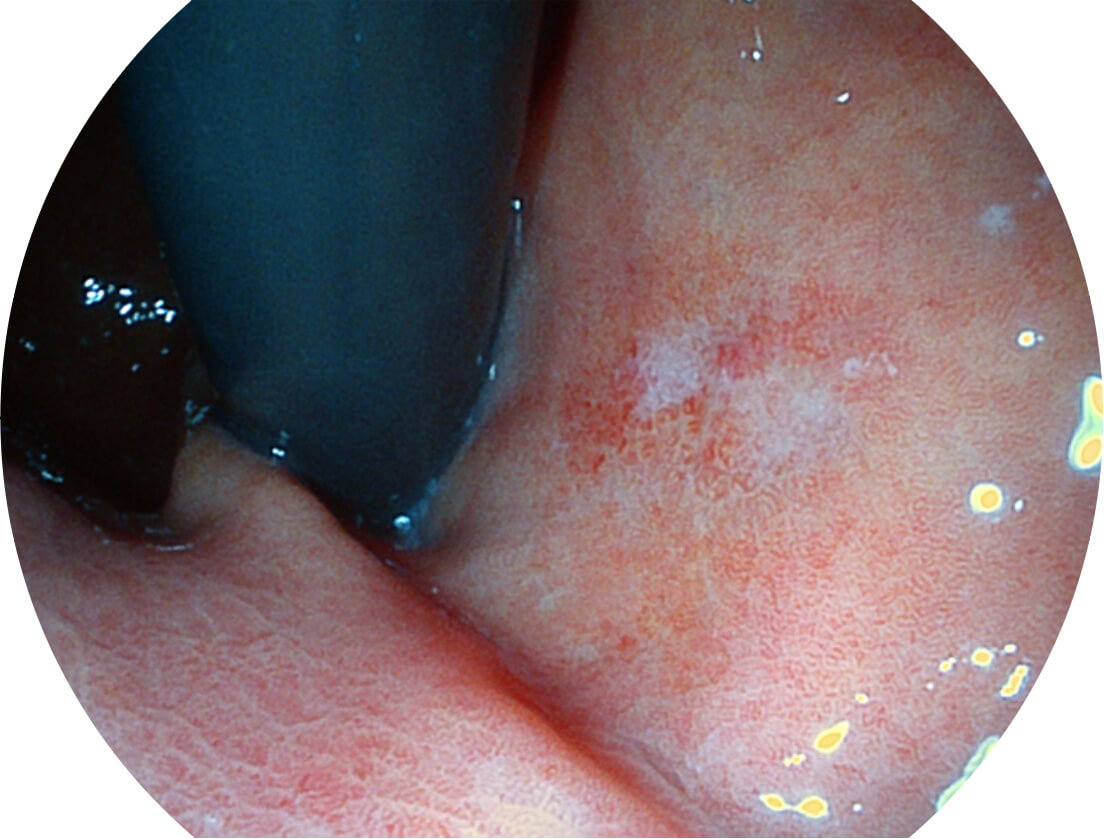

图像具有高亮度、高黏膜血管颜色对比度的特点,且不改变粘液、食物残渣、粪便的基本颜色,可在中远景下进行观察,助力消化道早期疾病的诊断。

白光图像

SFI图像